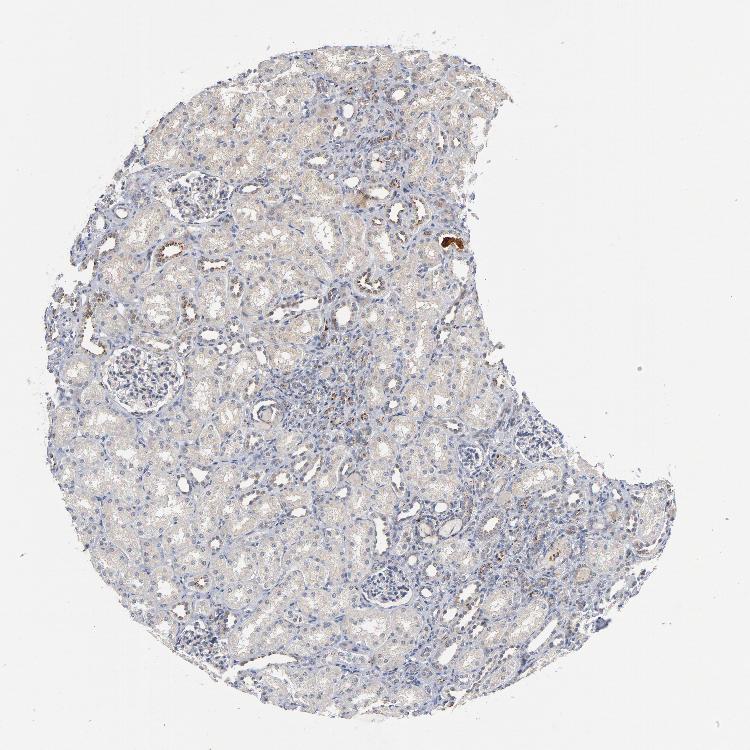

KIDNEY - Antibody stainingi

Antibody staining in the annotated cell types in the current human tissue is reported as not detected, low, medium, or high, based on conventional immunohistochemistry profiling in selected tissues. This score is based on the combination of the staining intensity and fraction of stained cells.

Each image is clickable and will lead to virtual microscopy that enables deeper exploration of all samples and also displays staining intensity scores, fraction scores and subcellular localization as well as patient and tissue information for each sample.

Antibody CAB004204Antibody CAB080295

Cells in glomeruli LowMedium

Cells in tubules MediumMedium